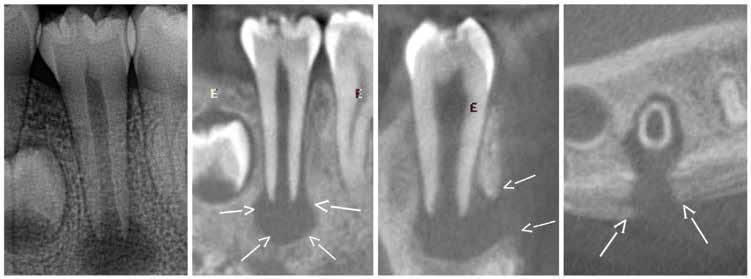

Magnetic resonance imaging (MRI) has been a staple in medicine and dentistry for many years. In dentistry, it serves a somewhat confined role in imaging the temporomandibular joints (TMJ) and occasionally the head and neck, including cysts or tumors. Dental MRI research and publications on these indications, as well as more “traditional” dental imaging tasks such as caries or periapical lesion detection, have progressed steadily since the mid-1980s, followed by a rapid increase in published papers in the early 2020s. These studies have long demonstrated the utility of MRI TMJ and cyst/tumor imaging, as well as the promise of MRI for essentially the entire range of dental imaging indications. Indications include caries, periapical disease, periodontal disease, growth and development/

The newly formed Orofacial MRI Center (OMRIC, dentistry.umn.edu/omric) at the University of Minnesota School of Dentistry is home to the first dental-dedicated MRI (ddMRI) unit in North America and the second installation of its kind in the world. Researchers Drs. Don Nixdorf and Laurence Gaalaas have an extensive track record in dental MRI research and development. Still, they are thrilled to have as an imaging tool one of the very first dental-dedicated MRI units, a Siemens MAGNETOM Free.

Max Dental Edition* MRI scanner. In collaboration with Dentsply Sirona and Siemens Healthineers, Nixdorf and Gaalaas secured a multi-year research agreement and constructed a physical imaging center around a Free.Max MRI unit. Beginning in early 2025, they initiated research studies to investigate the utility of ddMRI diagnosis in patients with endodontic, orthodontic and TMJ conditions. Such work will establish the utility of an experimental dedicated extraoral dental MRI coil and support proven indications for ddMRI imaging in endodontic, orthodontic, TMJ and other dental patient populations.

Proton density (left) and CBCT (right) images of apical lesion and furcation involvement at tooth #2. This tooth was clinically diagnosed with pulpal necrosis and a crack involving the furcation.

Proton density image showing improved image detail provided by dental dedicated MRI coil.

which perform notably better at imaging hard tissues such as bone and teeth, compared to more traditional MRI sequences.

While most dentists are likely familiar with the basics of how information is displayed on an MRI image, the adoption of ddMRI will require a mindset shift for virtually all dental team members who may utilize this new technology in their respective clinics. First, the grayscale is fundamentally different from that used for all X-raybased imaging. In MRI, soft tissues are commonly displayed as gray or bright white signals, while hard tissues, such as teeth and bone, are shown as very dark gray or black signals; air remains black. Furthermore, MRI offers the option to select from a variety of different sequences, each of which can produce a slightly different tissue grayscale and corresponding image. Some sequences, such as T1 or PD, do an excellent job of demonstrating detailed anatomical relationships. Other sequences, such as T2, do an excellent job of demonstrating the presence of fluid accumulation within tissues. Many available “Fat sat” or “STIR” sequences may selectively “zero out”, “suppress”, or “saturate” the signal of fat, which is traditionally very bright white on MRI images, to reveal the otherwise hidden signal from subtle fluid accumulation or inflammatory changes. Some of these specialized sequences may not accurately depict anatomic relationships, but are designed to be exceptionally sensitive to detecting inflammatory changes with a bright signal. The short T2 sequences mentioned above are beginning to depict the hard tissue differences between cortical bone and medullary bone, as well as the differences between tooth dentin and enamel. Developing, learning and using all these different sequence choices in concert is where the real research and diagnostic potential of ddMRI lies. t